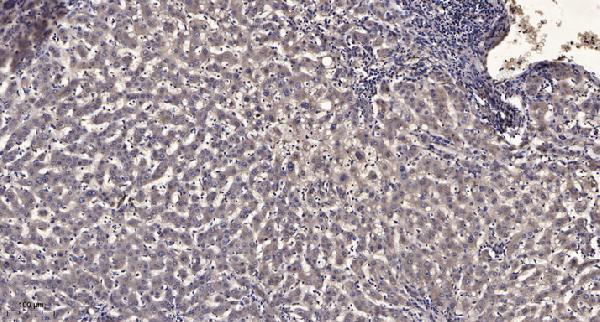

Facts about AMP deaminase 3.

| Gene Name: | AMPD3 |

| Uniprot: | Q01432 |

| Entrez: | 272 |

adenosine monophosphate deaminase (isoform E); adenosine monophosphate deaminase 3; AMP aminohydrolase; AMP deaminase 3; AMP deaminase isoform E; EC 3.5.4.6; Erythrocyte AMP deaminase; erythrocyte type AMP deaminase; erythrocyte-specific AMP deaminase; myoadenylate deaminase

88.812 kDA